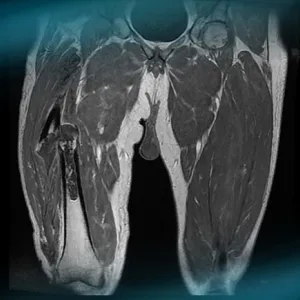

What are the therapeutic options in case of spontaneous pathological diaphyseal fracture of the right femur leading to the diagnosis of a dedifferentiated chondrosarcoma in a 52 year-old man? How would you manage this clinical case?